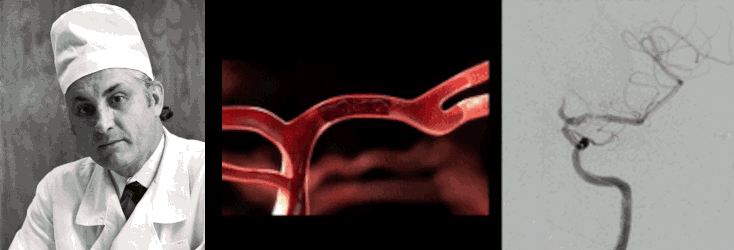

Путешествие по сосудам

Еще одним важным применением рентгеновской визуализации стала эндоваскулярная нейрохирургия, «отцом» которой признан наш соотечественник Федор Андреевич Сербиенко (рис. 24Б) [87], доказавший, что до мозговых сосудов можно добраться изнутри. Под контролем рентгенографии врач вводит тончайший катетер через бедренную артерию и ведет его прямо к патологическому очагу в сосудах мозга. Сегодня этот метод позволяет «заклеивать» аневризмы специальными композитами или устанавливать спирали, предотвращая смертельно опасные кровоизлияния без единого разреза на голове. Эндоваскулярные методики особенно актуальны для сосудистых аномалий, локализованных на нижней поверхности мозга, т.е. труднодоступных и глубоких.

В 1927 году португальский невролог Антониу Эгаш Мониш предложил вводить йодсодержащее рентгеноконтрастное вещество в мозговые сосуды и разработал метод церебральной ангиографии, который до сих пор активно используют сосудистые нейрохирурги (рис. 17В) [69]. Однако Нобелевскую премию Мониш получил не за этот метод, а за разработку лоботомии — запрещенного в настоящий момент метода отсечения трактов лобных долей от остальных частей мозга у душевнобольных пациентов [70], о котором мы еще поговорим в следующей главе.